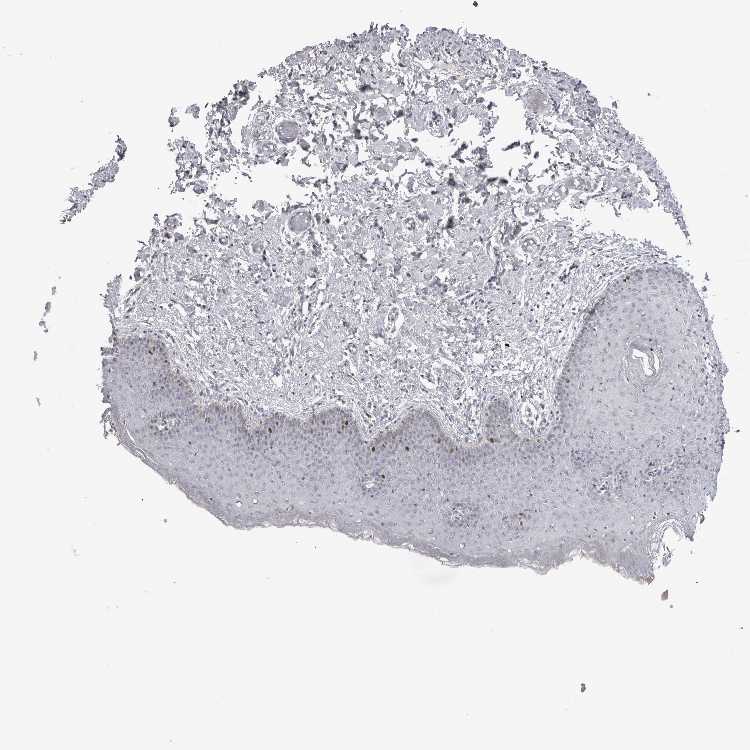

SKIN 1 - Antibody stainingi

Antibody staining in the annotated cell types in the current human tissue is reported as not detected, low, medium, or high, based on conventional immunohistochemistry profiling in selected tissues. This score is based on the combination of the staining intensity and fraction of stained cells.

Each image is clickable and will lead to virtual microscopy that enables deeper exploration of all samples and also displays staining intensity scores, fraction scores and subcellular localization as well as patient and tissue information for each sample.

Antibody HPA024205

Langerhans Low

Fibroblasts Not detected

Keratinocytes Medium

Melanocytes Low